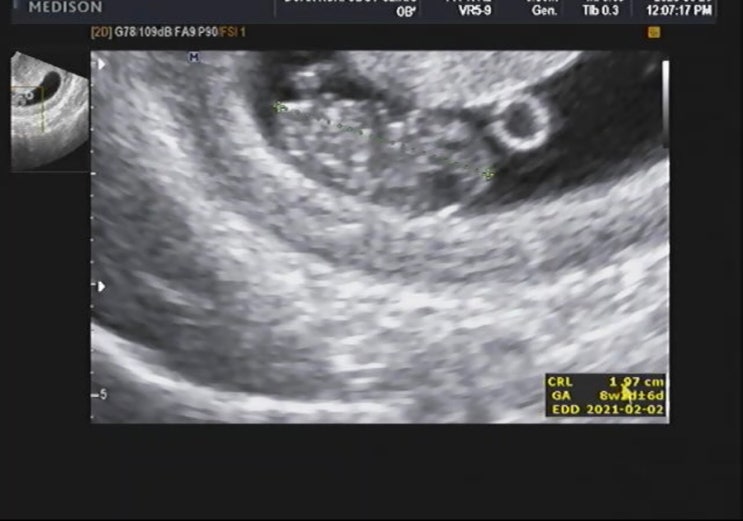

임신 8주차 증상 국민행복카드발급과 젤리곰ෆ

임신 7주차, 국민행복카드 발급 임신 7주차 20.6.16~ 폭풍입덧중이어서 증상 기록 자체가 없는 나의 임신 7...